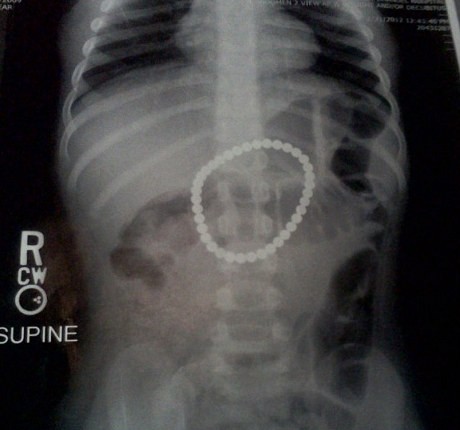

Ibunda Payton Bushell, bocah berumur 3 tahun itu, sangat terkejut ketika membawa putrinya yang sakit ke dokter. Hasil pemeriksaan sinar X menunjukkan bahwa anak perempuan itu telah menelan 37 magnet kecil berdaya tinggi. Dokter menduga, Payton telah menelan sebuah gelang. Sebabnya, hasil rontgen menunjukkan ada sebuah gelang dalam lambung balita tersebut.

Hasil pemeriksaan menunjukkan bahwa magnet-magnet tersebut mengganggu saluran pencernaan Payton. Menurut dokter, magnet berdaya tinggi tersebut telah merobek usus bagian bawah dan perut Payton.